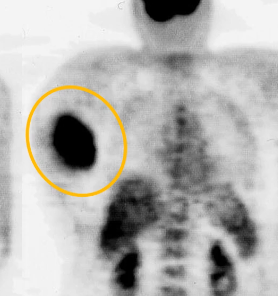

• Tumeur rare de la graisse brune (FDG avide)